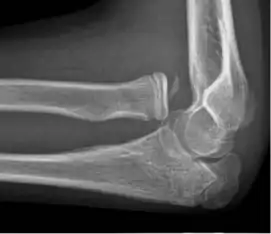

• Elbow: Posterior dislocation, 90% of all elbow dislocations[29]